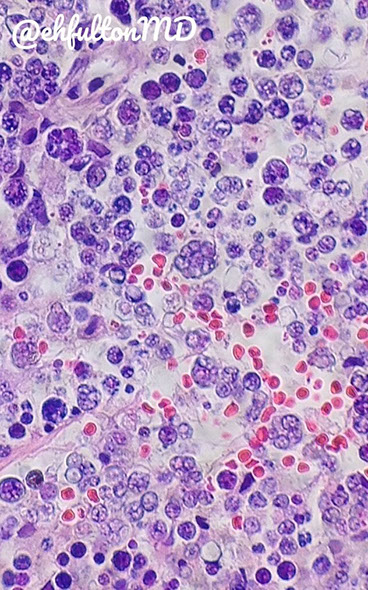

Micro: look for molluscum bodies (aka Henderson-Patterson) which are large keratinocytes c cytoplasmic, light red grainy inclusions that push the nucleus to the side

- dense infiltrate of lymphocytes may lead to thinking of lymphoma

Molluscum contagiosum